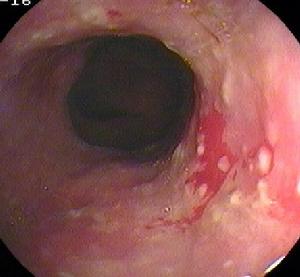

幽門管潰瘍2.容易並發出血:有報導約1/2的患者伴發出血,表現為嘔血或黑便,而且反覆出血,不易停止。分析其原因,系幽門弩的幽門括約肌頻繁而強烈收縮,使出血處形成的血痂容易脫落而易再發出血。

4.容易漏診:幽門管潰瘍行X線鋇餐檢查容易漏診,故走張行胃鏡檢查。胃鏡下可直接觀察到潰瘍的大小、形態及幽門有無梗阻、水腫等情況。

2、胃鏡檢查和黏膜活檢胃鏡檢查不僅可對胃十二指腸黏膜直接觀察、攝影,還可在直視下取活檢作病理和Hp檢測。它對消化性潰瘍的診斷和良、惡性潰瘍鑑別診斷的準備性高於X線鋇餐檢查。在潰瘍太小或太表淺,鋇餐檢查難以發現;鋇餐檢查發現的十二指腸球部畸形可有多種解釋難以確診;活動性上消化道出血是鋇餐檢查的禁忌證,內鏡檢查可確定其來源和性質。鋇餐檢查或內鏡下看似良性的GU中,大約5%實際是惡性的,反之少部分看似惡性的潰瘍,事實證明是良性的,不作活檢難以鑑別。此外,內鏡檢查還可發現伴隨潰瘍的胃炎和十二指腸炎。內鏡下消化性潰瘍多呈圓形或橢圓形,偶也呈線狀,邊緣光整,底部充滿灰黃色或白色滲出物,周圍黏膜可有充血、水腫,有時見皺襞向潰瘍集中。內鏡下潰瘍可分為活動期(A)、癒合期(H)和瘢痕期(S)三個病期,其中每一病期又可分為1和2兩個階段。